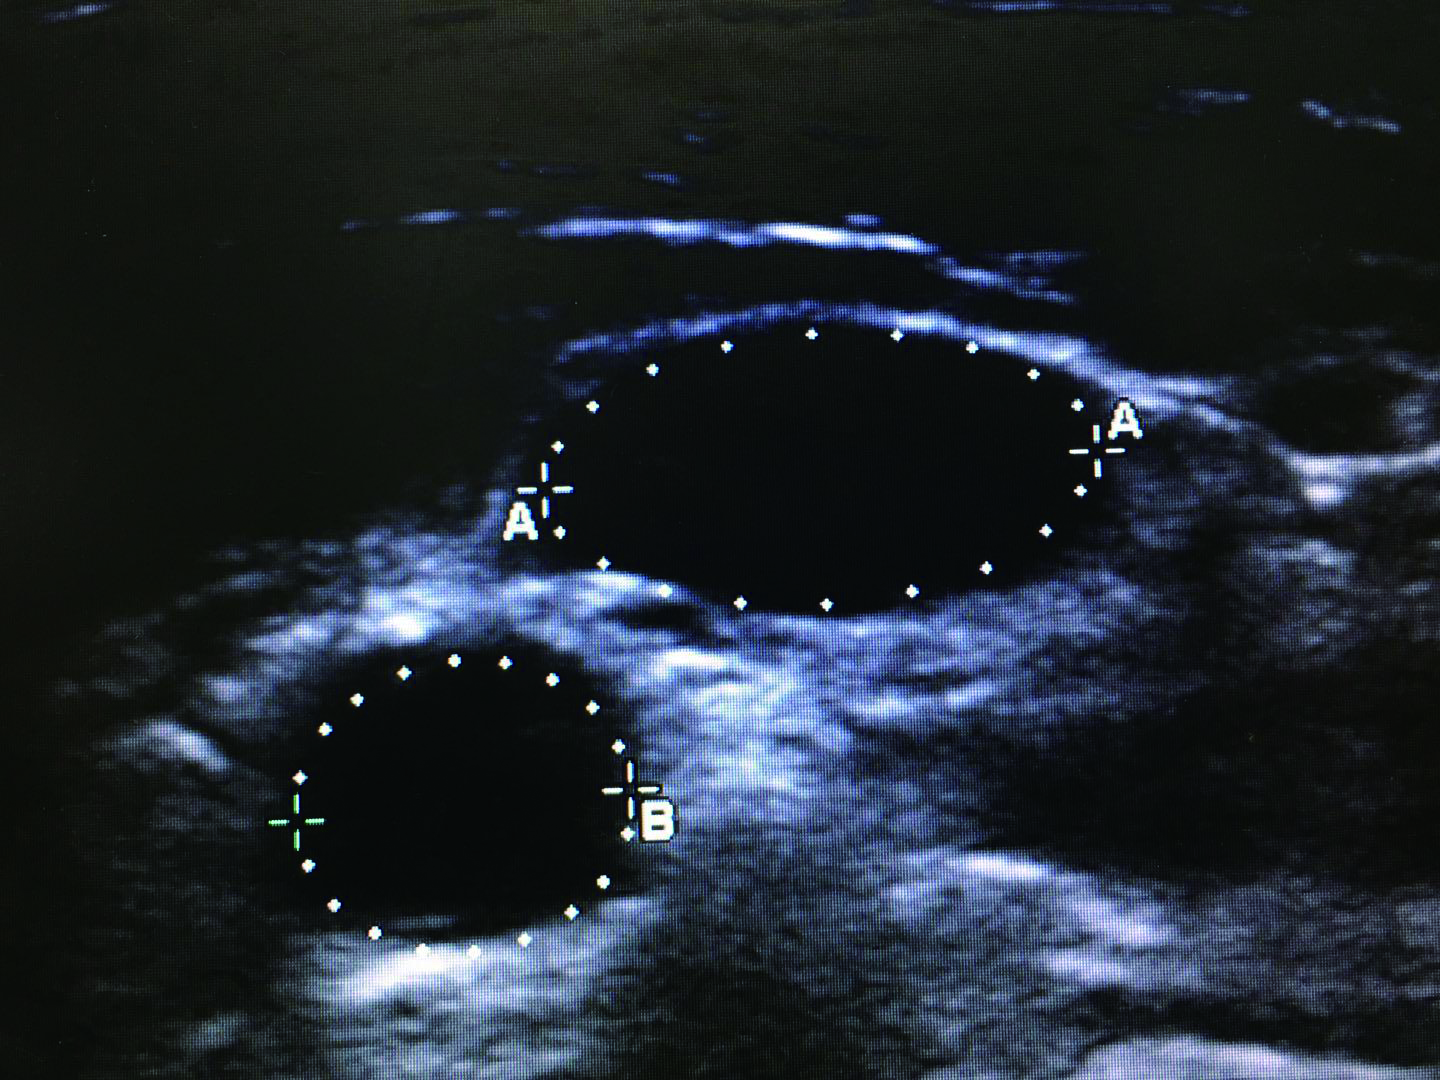

1.2.1 IJV/CCA截面积比值测量及计算方法患者取去枕平卧位,充分暴露颈部,选择甲状软骨最低位,将超声探头轻放于颈部血管处,分别测得头部正位时,双侧颈内静脉与颈总动脉横截面,冻结超声图像,使用电子标记界定颈内静脉和颈总动脉横截面的长径,同时,使用电子标记测得横截面周长,并且使用预先加载到超声单元中的程序计算颈部血管的横截面积,最后计算IJV/CCA截面积比值(图 1)。

|

| 图 1 超声电子标记的颈内静脉(A)和颈总动脉(B)周长 Figure 1 The perimeter of the internal jugular vein (A) and common carotid artery (B) electronic marked by ultrasound |

|

|